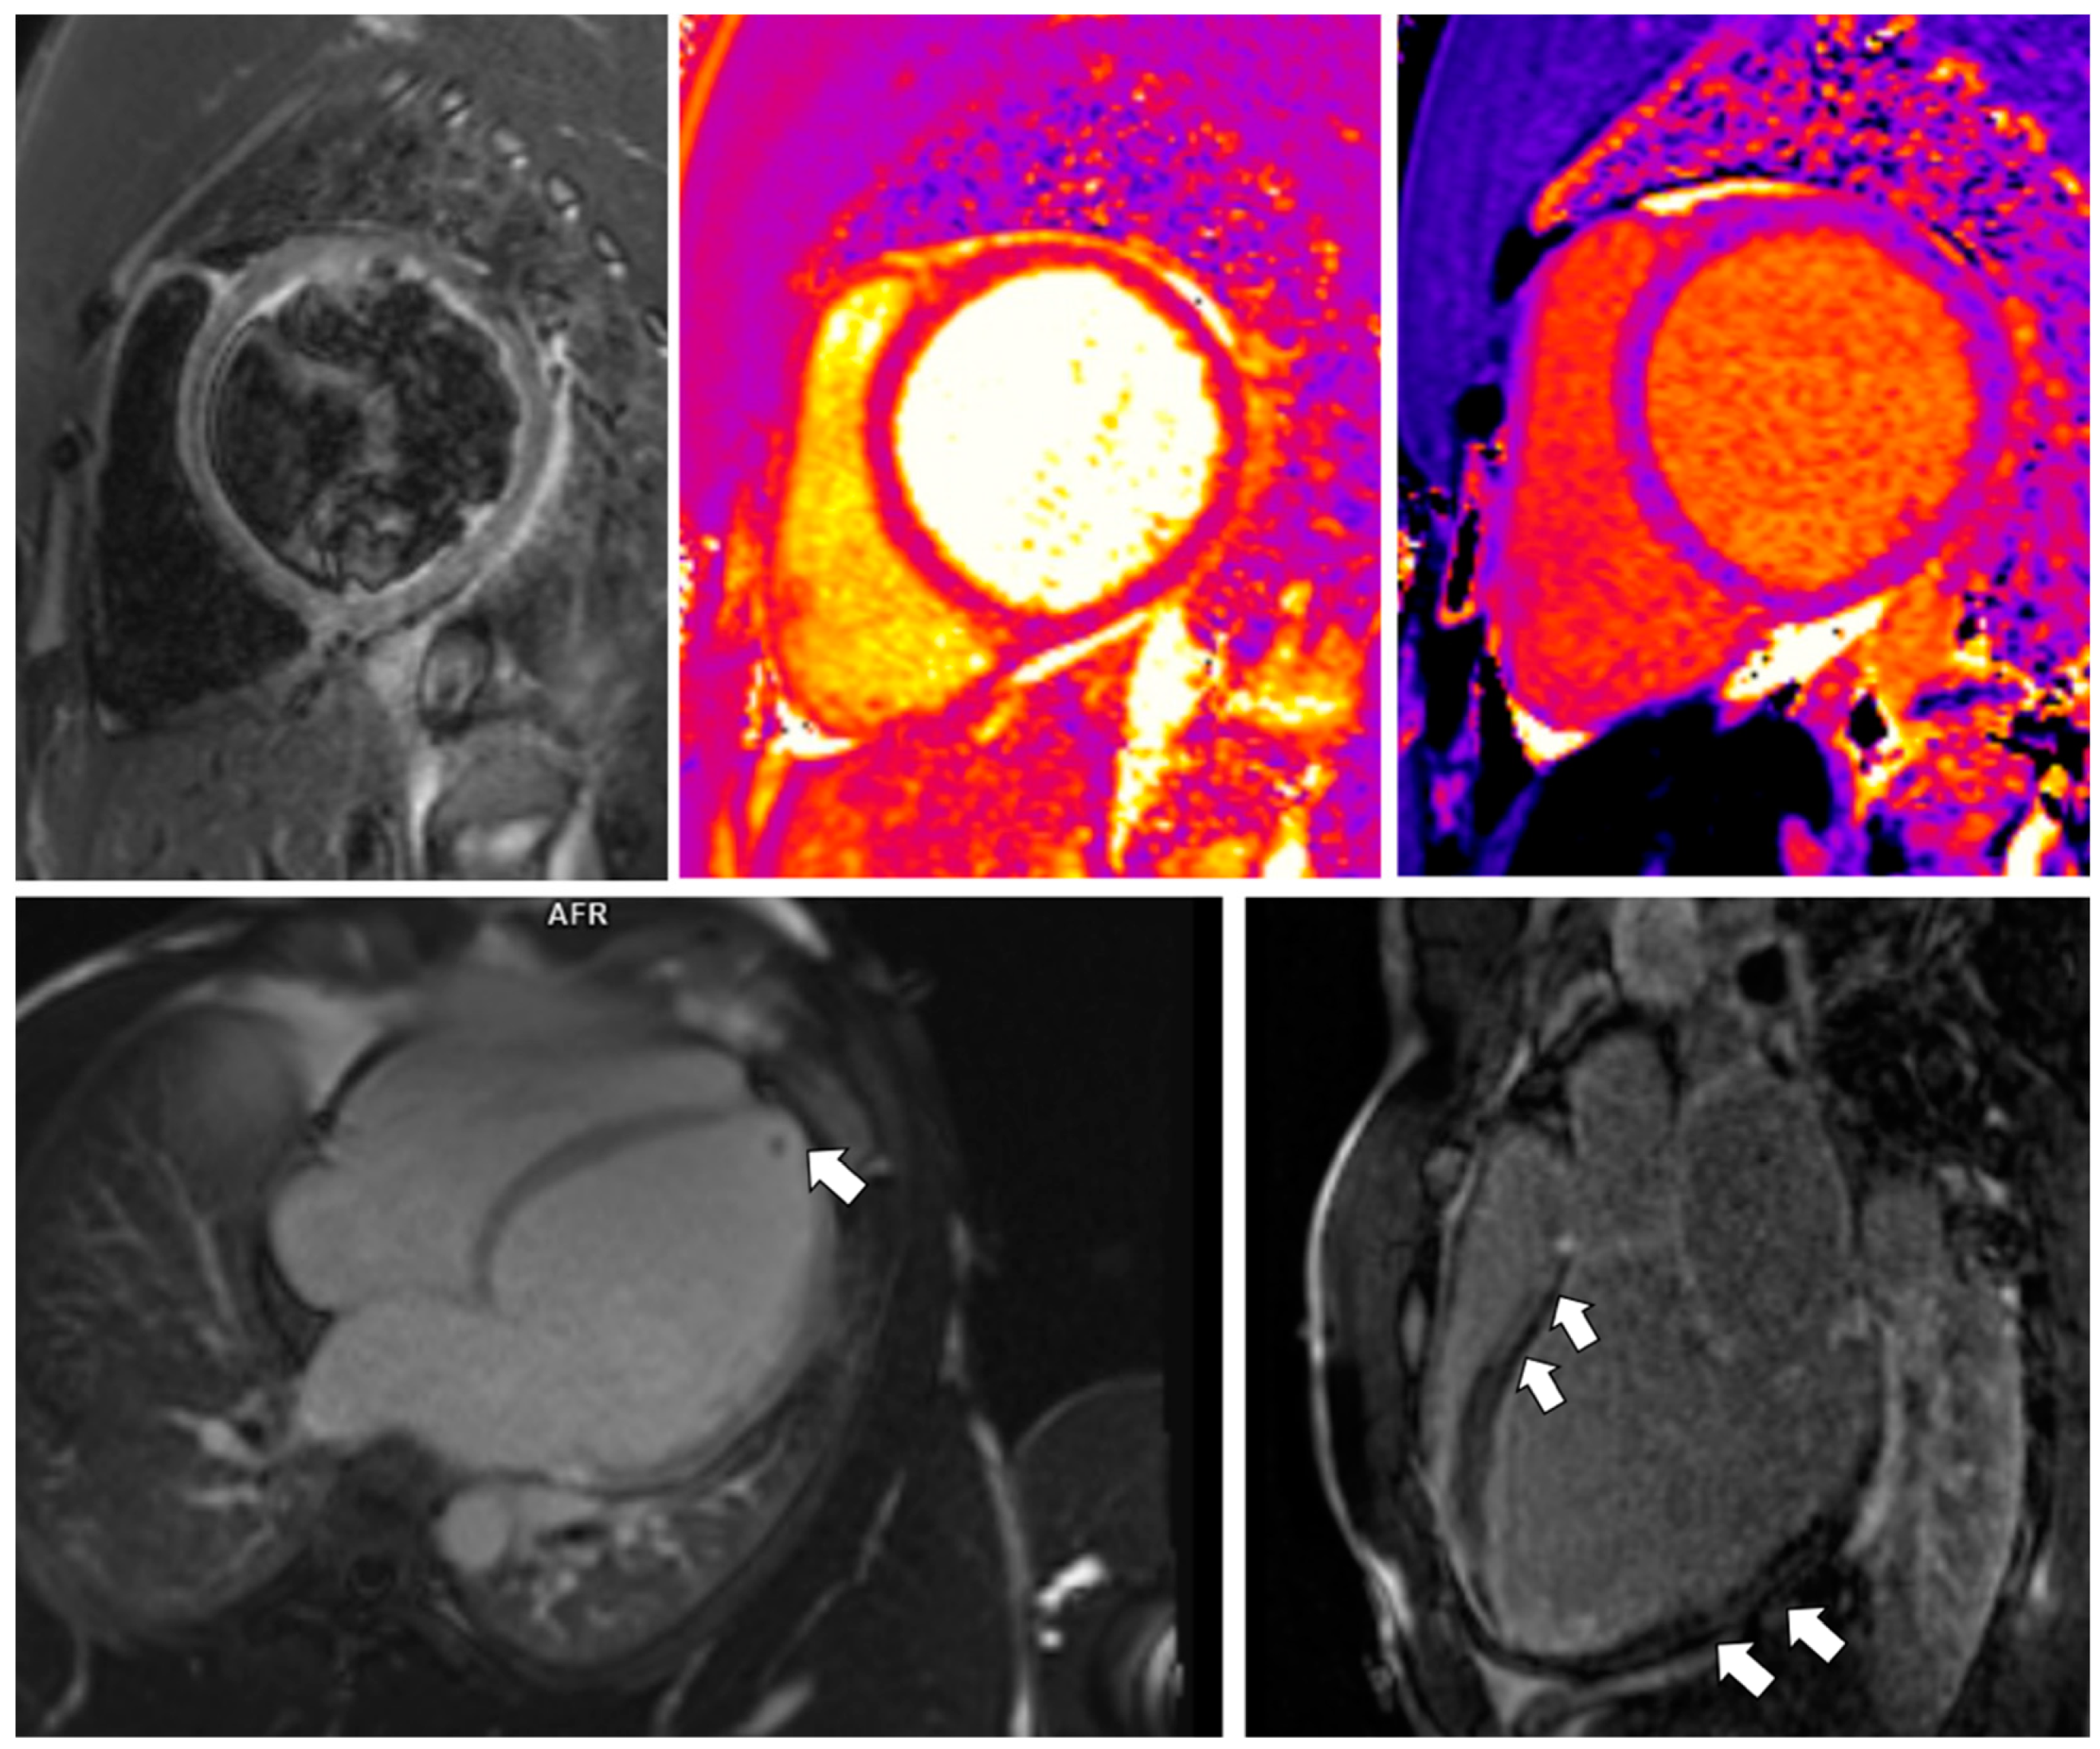

3.2. Case 2

| Case 1 (CMR 1) | Case 1 (CMR 2) | Case 2 | Case 3 | |

|---|---|---|---|---|

| LVEDV (mL; normal 83–207) | 206 | 227 | 489 | 215 |

| LVEDVI (mL/m2; normal 47–107) | 99 | 110 | 242 | 106 |

| LVEF (%; normal 51–76) | 49 | 53 | 14 | 26 |

| LVSV (mL; normal 55–127) | 100 | 121 | 67 | 55 |

| RVEF (%, normal: 42–72) | 53 | 47 | 21 | 34 |

| Native T1 (ms; normal 993 ± 21) | not measured | 971 | 1014 | 1012–1080 |

| T2 (ms; normal 44 ± 2.4 ms) | not measured | 47 | 46 | 48 with local increase subepicardially up to 53 ms |

| LGE (segments) | subepicardial

| not detected | intramural-subepicardial

| intramural—subepicardial

|

| ECV (%; normal 25.3 ± 3.5) | not calculated | 26 | 30 | 30 |